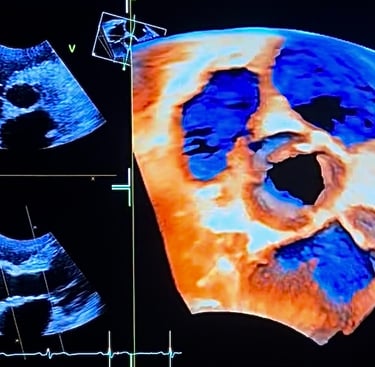

Echographie cardiaque (ETT)

Cette formation s’adresse à tous ceux qui souhaitent se former ou se perfectionner en échographie cardiaque. Qu’il s’agisse d’approfondir la 4D, la quantification des insuffisances valvulaires ou encore l’analyse des cardiomyopathies. Conçue sur mesure, elle accompagne aussi bien les professionnels en formation (DIU/DU d’échographie cardiovasculaire non invasive) que les praticiens déjà expérimentés. Vous y trouverez de nombreux cas cliniques concrets, des explications claires et des outils pratiques.